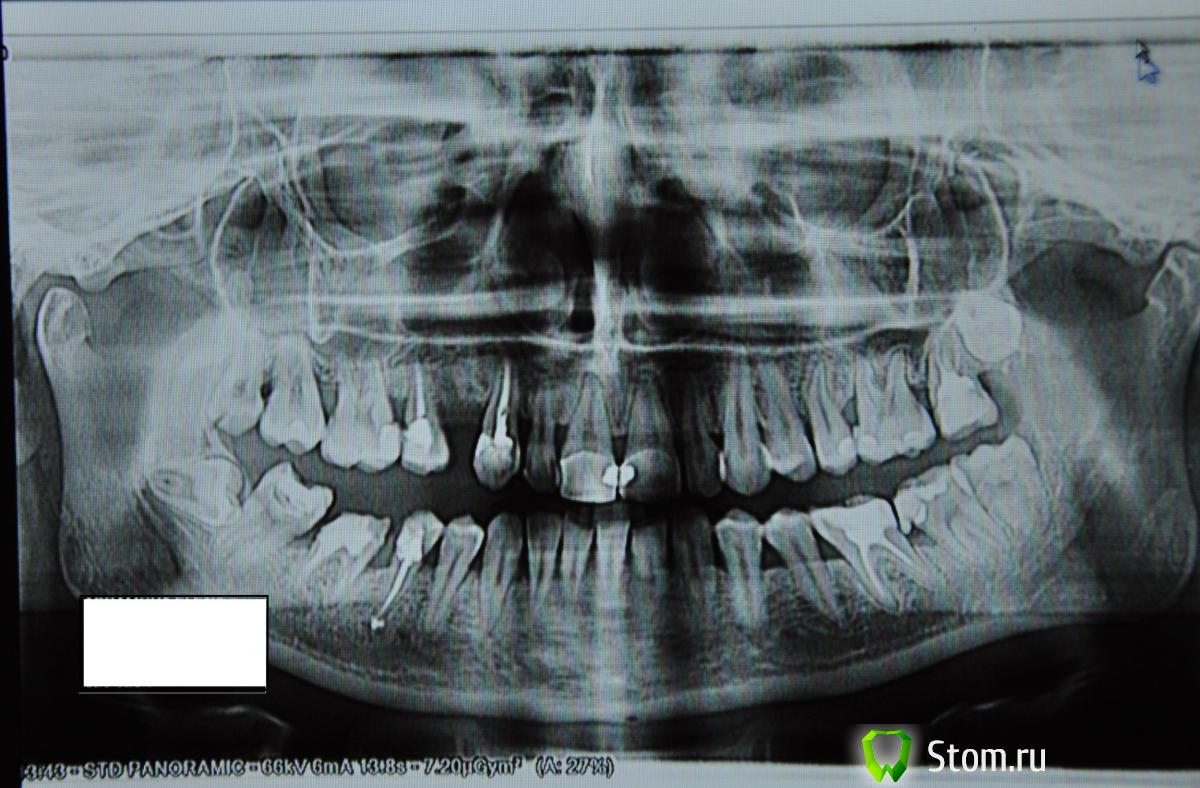

MTG Опубликовано 30 января, 2012 Поделиться Опубликовано 30 января, 2012 Здравствуйте! Можно ли по снимку сказать есть ли пародонтит/пародонтоз и определить его стадию? Нужно ли удалить проросший зуб мудрости, если он меня не беспокоит? На 7ке вверху выпала часть пломбы (не знаю как правильно написать номер этого зуба, на снимке получается справа вверху), врач рекомендует удалить его и поставить туда имплантант, можно ли избежать удаления? Заранее спасибо за ответ. Ссылка на комментарий

ger_berra Опубликовано 30 января, 2012 Поделиться Опубликовано 30 января, 2012 Диагноз "пародонтит" только по снимку поставить нельзя.Но все рентгенологические признаки у Вас есть.Стадия(по снимку) как минимум средней тяжести.На счёт 7-ки локализацию верно указали? Ссылка на комментарий

MTG Опубликовано 31 января, 2012 Автор Поделиться Опубликовано 31 января, 2012 сходила к врачу, так как не смогла найти русскоговорящего, с 10 раза поняла, что пародонтит/пародонтоз 3 степени, закругленной штучкой залез под десну и сказал что 5 мм, через 2 года все зубы выпадут, требуется операция, будет резаться десна, 5-10 швов, потом будет одеваться на верхнюю и нижнюю челюсти типа коронки только для всех зубов, я в шоке , действительно все так плохо? для чего нужно на мои уже имеющиеся зубы что-то одевать после операции? Ссылка на комментарий

ger_berra Опубликовано 1 февраля, 2012 Поделиться Опубликовано 1 февраля, 2012 сходила к врачу, так как не смогла найти русскоговорящего, с 10 раза поняла, что пародонтит/пародонтоз 3 степени, закругленной штучкой залез под десну и сказал что 5 мм, через 2 года все зубы выпадут, требуется операция, будет резаться десна, 5-10 швов, потом будет одеваться на верхнюю и нижнюю челюсти типа коронки только для всех зубов, я в шоке , действительно все так плохо? для чего нужно на мои уже имеющиеся зубы что-то одевать после операции?Возможно,что это не коронки,а специальные шины.Не пугайтесь,их можно сделать незаметными. Ссылка на комментарий